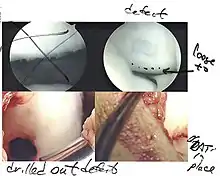

Intact lesions

If non-surgical measures are unsuccessful, drilling may be considered to stimulate healing of the subchondral bone. Arthroscopic drilling may be performed by using an antegrade (from the front) approach from the joint space through the articular cartilage, or by using a retrograde (from behind) approach through the bone outside of the joint to avoid penetration of the articular cartilage. This has proven successful with positive results at one-year follow-up with antegrade drilling in nine out of eleven teenagers with the juvenile form of OCD,[53] and in 18 of 20 skeletally immature people (follow-up of five years) who had failed prior conservative programs.[54]

Hinged lesions

Pins and screws can be used to secure flap (sometimes referred to as hinged) lesions.[55] Bone pegs, metallic pins and screws, and other bioresorbable screws may be used to secure these types of lesions.[56]

The three methods most commonly used in treating full thickness lesions are arthroscopic drilling, abrasion, and microfracturing.